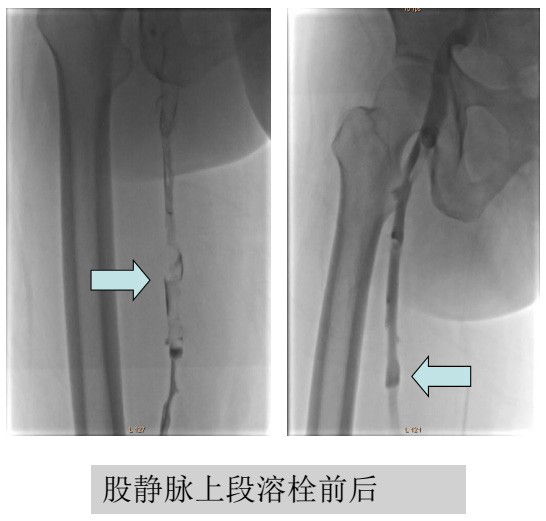

导管溶栓是通过各种方式将导管放到血栓内部,局部注射

溶栓药物增强溶栓效果。在置入导管之前,需要放下腔静脉滤 器保护,以避免肺栓塞。溶栓后复查 DSA造影,如果发现髂静脉有狭窄,还需要用球囊或支架解决。导管溶栓的缺点主要 是费用高。

经皮肤穿刺到深静脉(常用的例如腘静脉),将溶栓导管 插到血栓内部,经导管给药后,溶栓药物直接进入到血栓内部,从而大大增强溶栓效果。并且,溶栓导管有多个侧孔,药物注 射后可以在血栓内部分布更为广泛,效果更好。而且,由于局 部有效药物多,全身就不需要一味增大药物剂量,从而降低出 血风险。

为了减少副损伤,同济医院血管外科组常规采取超声引导下穿刺腘静脉,造影后插入溶栓导管,术中和术后均经导管给药。如果发现髂静脉狭窄,可初步做球囊扩张,以增加效果。后续根据病人经济能力,以及溶栓效果,酌情考虑是否做髂静脉支架植入。